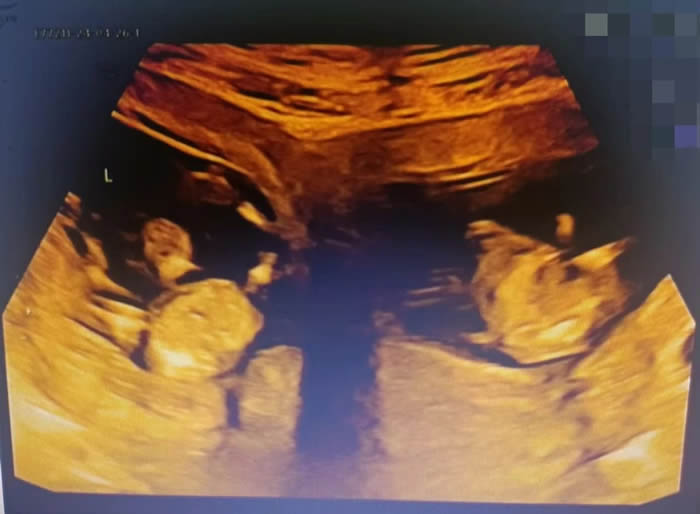

近日,徐州市婦幼保健(jiàn)院產科九病區聯合多學科,為一名先天擁(yōng)有雙子(zǐ)宮的女性施行剖宮產術,成功助其誕下一對龍鳳胎。在兩個子宮內都(dōu)分別自然受孕,且為龍鳳胎極為罕見,迄今(jīn)為止國內外都鮮有報道,根據“醫學界”記載,雙子宮畸形的發生率(lǜ)約為1/3萬-1/1萬,同時自然受孕的幾率在1/100萬-1/5000萬不等

更令人意外的是,早孕期超聲提示,曉曉腹中竟有兩(liǎng)個胎兒(ér),且兩(liǎng)個孩(hái)子各居“一室(shì)”,互不幹擾(rǎo)。“在我近30的職業生(shēng)涯中,還從未遇到過(guò)雙子宮雙胞胎的孕婦。雙子(zǐ)宮女性妊娠風險非常多,很可(kě)能會(huì)出現早產(chǎn)、胎兒生長受限、子宮破裂等情況,每種風(fēng)險都不容小覷。”產科九病區主任吳惠瑩如是說。